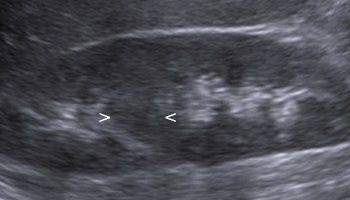

USG układu moczowego i prostaty

Jest to podstawowe badanie obrazowo-diagnostyczne w każdym podejrzeniu choroby nerek, pęcherza moczowego i prostaty. Jest elementem badania jamy brzusznej, lecz może być zlecone przez lekarza urologa jako oddzielne badanie. Obejmuje ocenę nerek, dróg moczowych, pęcherza moczowego oraz prostaty u mężczyzn. Jest badaniem podstawowym w rozpoznawaniu kamicy nerkowej, zastoju w nerkach, chorób rozrostowych nerek i pęcherza moczowego, kamicy w moczowodzie czy pęcherzu moczowym. Podczas tego badania ocenie podlega również wielkość gruczołu krokowego.

Część zdjęć pochodzi ze strony www.ultrasound-images.com